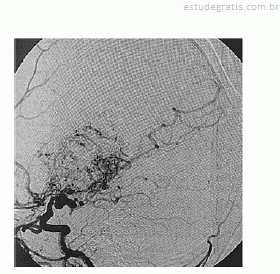

Paciente de 16 anos de idade, do sexo feminino, de asscendência japonesa, com deficits neurológicos progressivos iniciados ainda na infância, tem diagnóstico prévio de anemia falciforme. Realizou exame complementar de imagem do encéfalo, apresentado na reprodução acima. Há suspeita de doença de Moyamoya.

Em relação ao caso descrito, julgue os itens a seguir.

Os vasos extracranianos são potenciais doadores para revascularizacões.Comentários